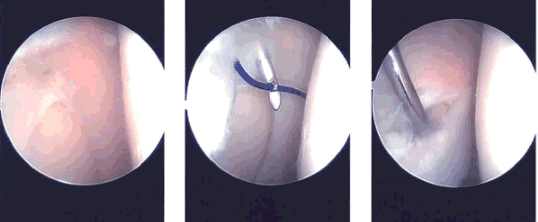

El examen del compartimento tibiofemoral lateral mostró desgarros en el cuerno anterior así como desgarros parciales en la raíz anterior. El desgarro en el cuerno anterior estaba en la zona rojo-blanca y se decidió repararlo. Se realizó desbridamiento de la raíz anterior del menisco lateral.

El desgarro se preparó con el uso de raspa meniscal y afeitadora. Se planificó una reparación desde el exterior. Se abrió el reparador meniscal y la aguja recta se pasó percutáneamente lateralmente a través del desgarro menisco. La aguja de la sonda se adelantó al lado de la aguja recta a través del desgarro.

Una vez colocada, la caja se sacó de la aguja de la sonda y se pasó la sutura PDS a través de la aguja recta. Se recuperó la sutura PDS. Se realizó una incisión en la piel que conectaba las dos suturas.

La sutura PDS fue reemplazada por el FiberWire #2-0. La reparación fue revisada artroscópicamente y se encontró en una posición satisfactoria. La sutura estaba nuda por fuera.

Imágenes intraoperatorias